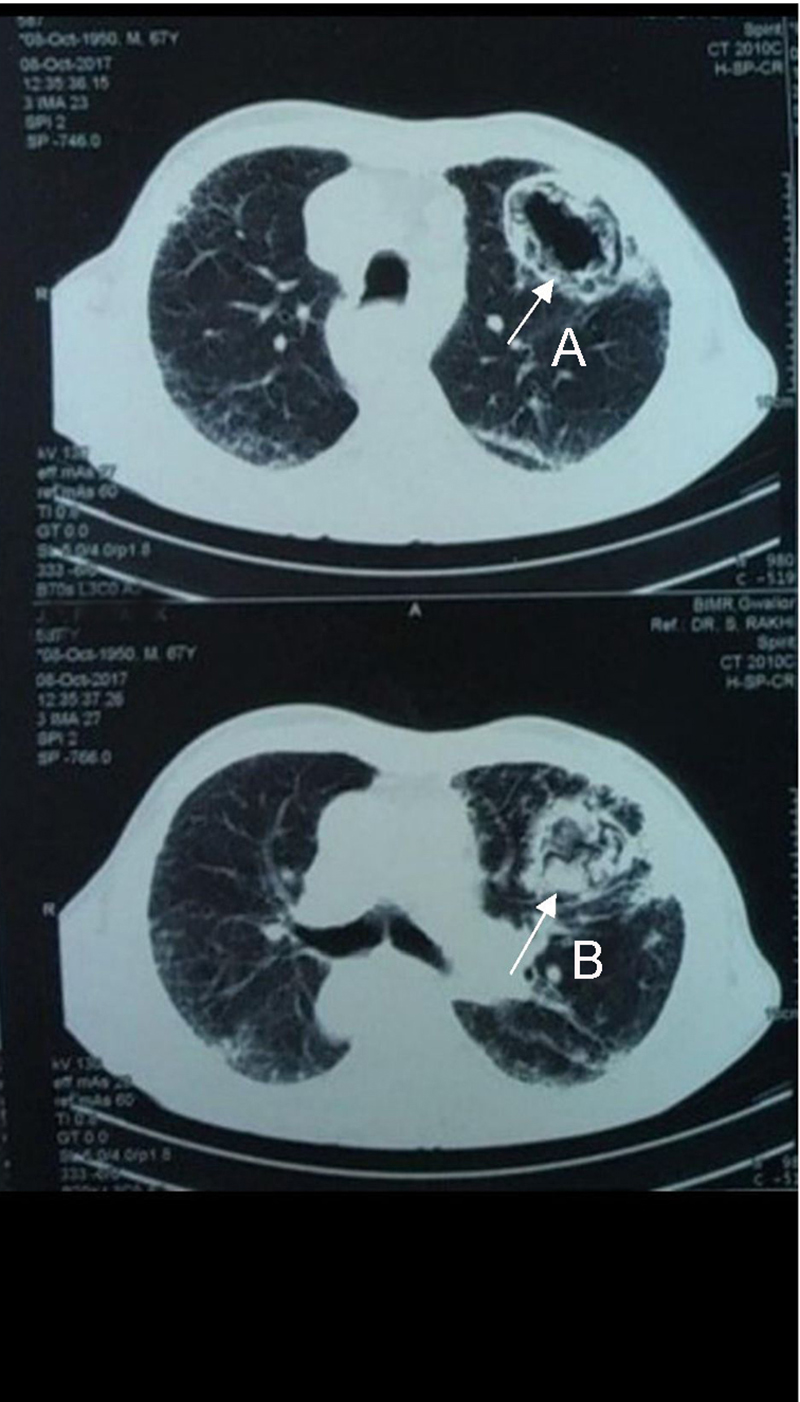

Ziel Nelson stain, a nucleic acid amplification test, and liquid culture were negative for AFB. Review of the serial x-rays over the previous 9 months (Figure 1) showed a cavity in the left mid zone in which the wall progressively increased in size and thickness (Figure 2). Contrast-enhanced computed tomography (CECT) of the chest during the eighth month of treatment revealed a nonspecific interstitial pneumonia (NSIP) pattern with a non-communicating cavity (a large necrobiotic nodule) with a soft tissue collection along its wall (Figure 3A) and collection of soft tissue in the cavity (Figure 3B). Chest x-ray taken 2 months later (tenth month since anti-tubercular treatment initiation) at the institute showed the presence of an air crescent in the same cavity (Figure 4). In view of his history of small joint pains, the patient was worked up for rheumatoid arthritis. Investigations revealed a strongly positive RF and ANA; however Anti-CCp was negative. Total IgE (543 IU/ml), serum specific IgE (3.29 KUA/L) and IgG(>80IU) for Aspergillus fumigatus were high. A diagnosis of RA with ILD with cavitating rheumatoid nodule containing an aspergilloma was made.

Figure 3

Figure 3. (A) Arrow showing Mycelial fronds on cavity wall; (B) Arrow showing collection of fronds in cavity after detachment from wall at month 8 of ATT initiation.